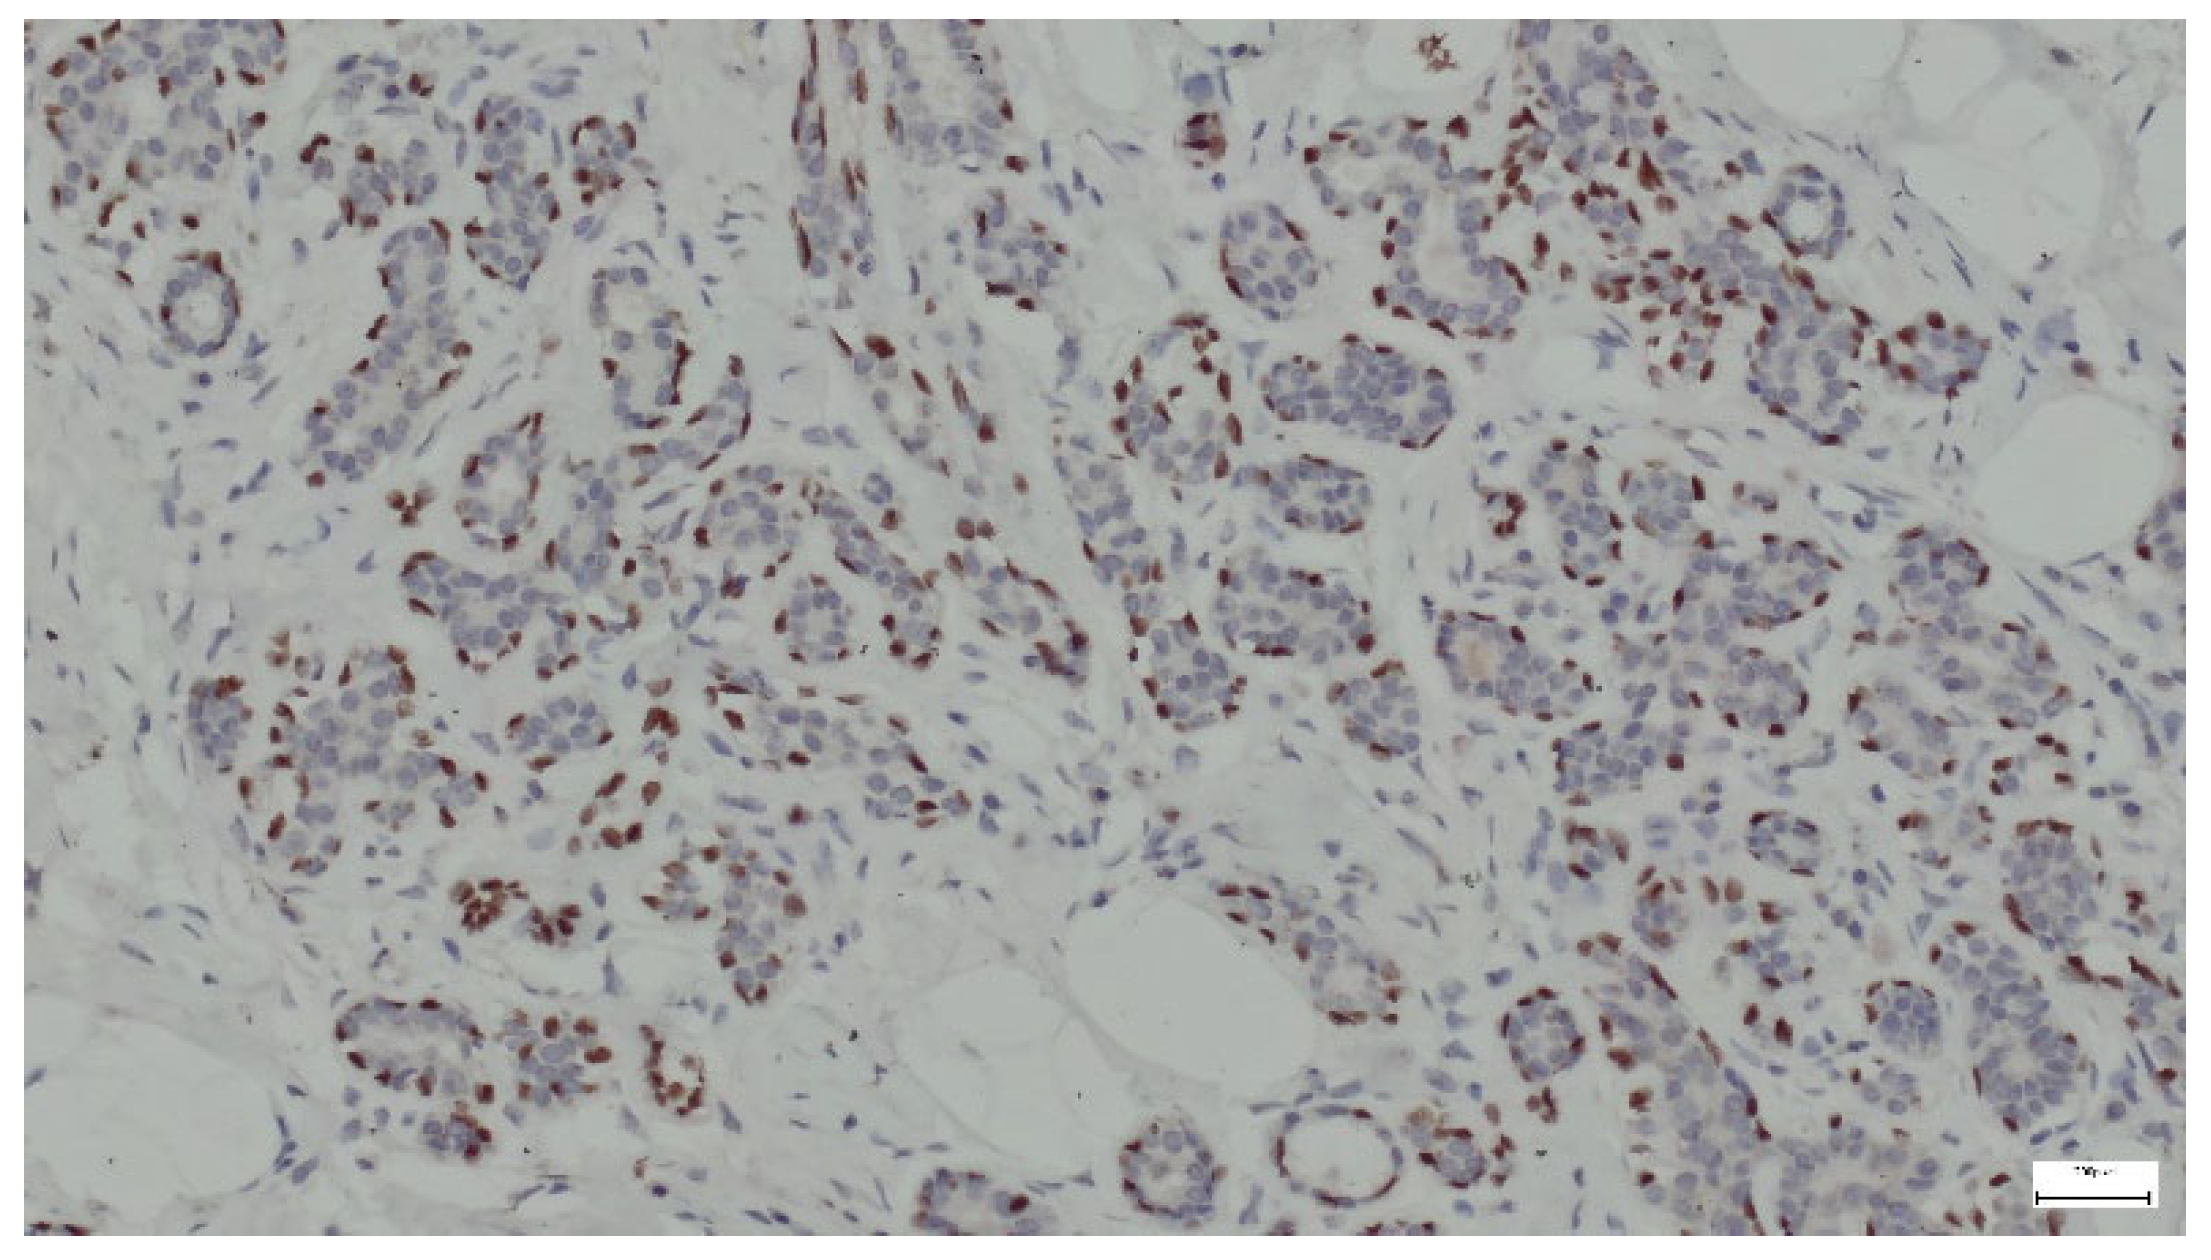

Breast hamartomas often express estrogen receptors (ER), that can be detected in the epithelial cells lining the ducts and lobules within the hamartoma. ER expression was found in all tissue samples (Figure 13).

Figure 13. ER lining the ducts and lobules in breast hamartoma (anti-ER, ×10).

In addition to histological evaluation, breast hamartoma can be confirmed by IHC, where glandular components that contain normal breast ducts and lobules are highlighted by ER, SMA, and p63. Immunostaining aids in the differentiation of breast hamartomas from malignant lesions and contributes to a detailed characterization of these benign entities. ER expression in breast hamartomas can indicate hormone responsiveness, similar to other benign and malignant breast lesions. ER can also be expressed in the stromal component of the hamartoma, though this is less common. Smooth muscle actin (SMA) staining in breast hamartomas can help identify the presence and distribution of myoepithelial cells around glandular structures. SMA can also stain myofibroblasts in the fibrous stroma of breast hamartomas. The staining can highlight pericytes and smooth muscle cells in the walls of blood vessels within the hamartoma [40]. p63 is a member of the p53 family of transcription factors and is involved in the development and maintenance of epithelial tissues. It is commonly used as a marker for myoepithelial cells in the breast and other tissues. The detection of a continuous layer of p63-positive myoepithelial cells around ducts and lobules supports the diagnosis of a benign lesion [40].